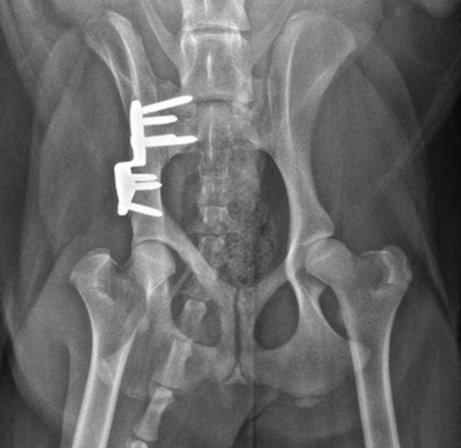

2.2.2 Beckenschwenkosteotomien (TPO/DPO)

Bei den 2- bzw. 3-fachen Beckenschwenkosteotomien werden Knochenschnitte an bestimmten Stellen des Beckens ausgeführt, um die Beckenpfanne mithilfe einer speziellen Knochenplatte und Schrauben seitlich neu auszurichten und damit eine reduzierte Laxizität, verbesserte Kongruenz und Reduktion der fokalen Überlastung zu erzielen. Der Eingriff ist nicht bei allen Patienten möglich/effektiv und wird im Regelfall nur innerhalb des ersten Lebensjahres durchgeführt.